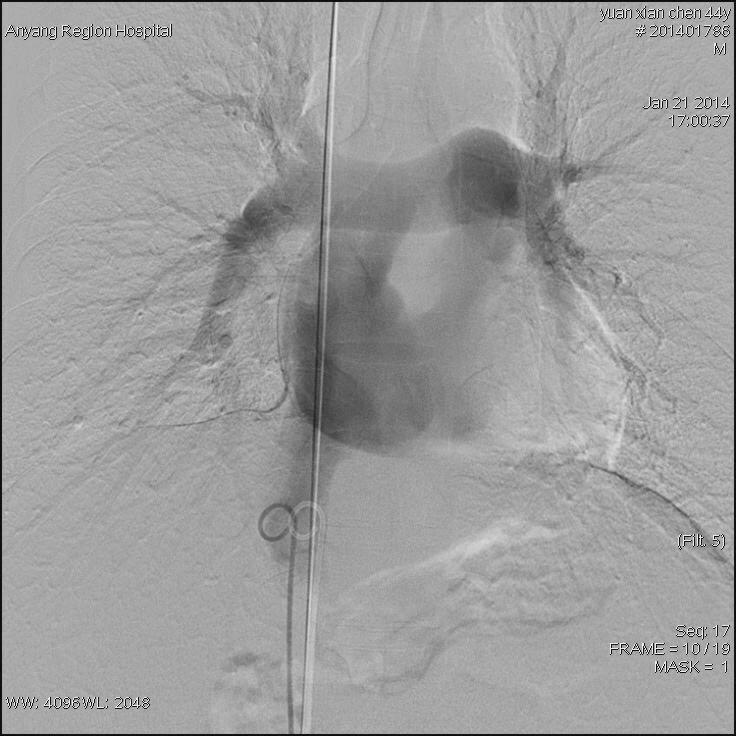

接受治疗的是一位44岁男性患者,该患者常年消化不良,身体异常瘦弱,肝脾肿大,双下肢静脉曲张合并腹壁静脉曲张,经核磁影像检查,诊断为布加综合征,考虑为下腔静脉肝后段膜性闭塞病变。我院介入科主任高毅组织科室医务人员认真研究患者病情,并详细制定出多种介入开通方案。1月21日,为患者进行了介入治疗。手术中,经穿刺股静脉与颈内静脉双向造影后,进一步明确了该患者为膜性闭塞。采用破膜针开通闭塞段,引入加硬导丝,交换引入较大球囊扩张后,患者下腔静脉瞬间畅通,下腔静脉压力明显下降,下肢静脉及腹壁静脉曲张立即消失,六小时后患者即下床活动,困扰患者多年的头晕等症状也随之消失。